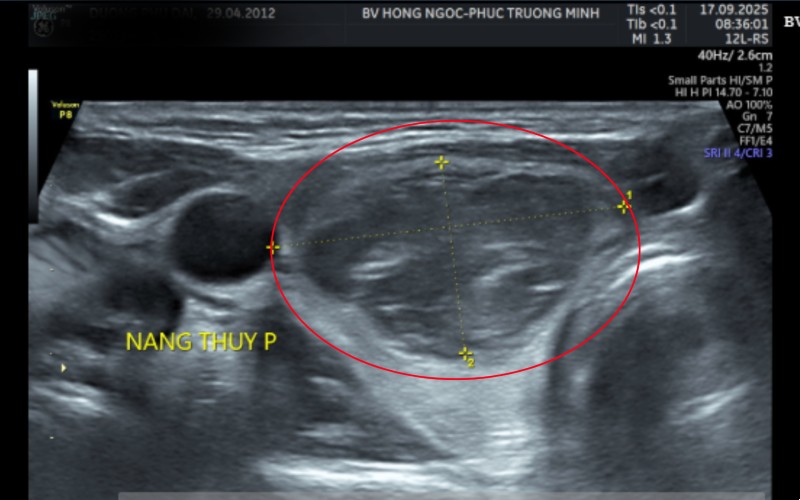

Thăm khám tại Bệnh viện Đa khoa Hồng Ngọc, kết quả siêu âm cho thấy bệnh nhi có khối u ở thùy phải tuyến giáp kích thước hơn 3 cm. Kết quả chọc hút tế bào bằng kim nhỏ (FNA) trước mổ cho thấy nghi ngờ ung thư tuyến giáp thể nhú nhóm V theo phân loại Bethesda.

| Kết quả siêu âm cho thấy khối u lớn hơn 3 cm (Nguồn ảnh: Bệnh viện Đa Khoa Hồng Ngọc) |